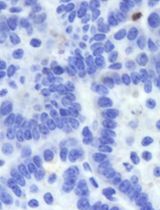

Thymidine Kinase from human Herpes simplex virus type 1 (HSV1-TK) in combination with specific substrate prodrug nucleotide analogue ganciclovir (GCV) has been widely used as suicidal therapeutic gene for cancer gene therapy. HSV1, and its mutant (HSV1-sr39TK) with improved substrate specificity, were used as reporter genes for PET-imaging of various biological functions in small animals, by combining with radiolabeled substrates such as 18F-FHBG and 124I-FIAU. 3H-Penciclovir (PCV) uptake assay is a method of choice used to determine the expression level of HSV1-TK in mammalian cells and tissues. HSV1-TK phosphorylate PCV and result in the formation of penciclovir monophosphate, and its subsequent phopsphorylation by cellular TK lead to the formation of penciclovir triphosphate, which is trapped selectively in cells express HSV-TK. 3H-Penciclovir enables the detection of penciclovir uptake of mammalian cells and tissues by radioactive procedures such as scintillation counting. Here we describe the protocol to carry out 3H-Penciclovir uptakes in mammalian cells.